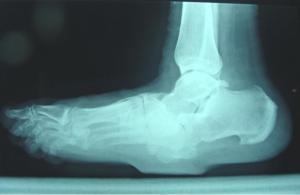

Los rayos X también son fundamentales para tener un diagnostico, en los cuales se muestra imágenes de una osteoartirtis muy severa con deformidad y destrucción articular.